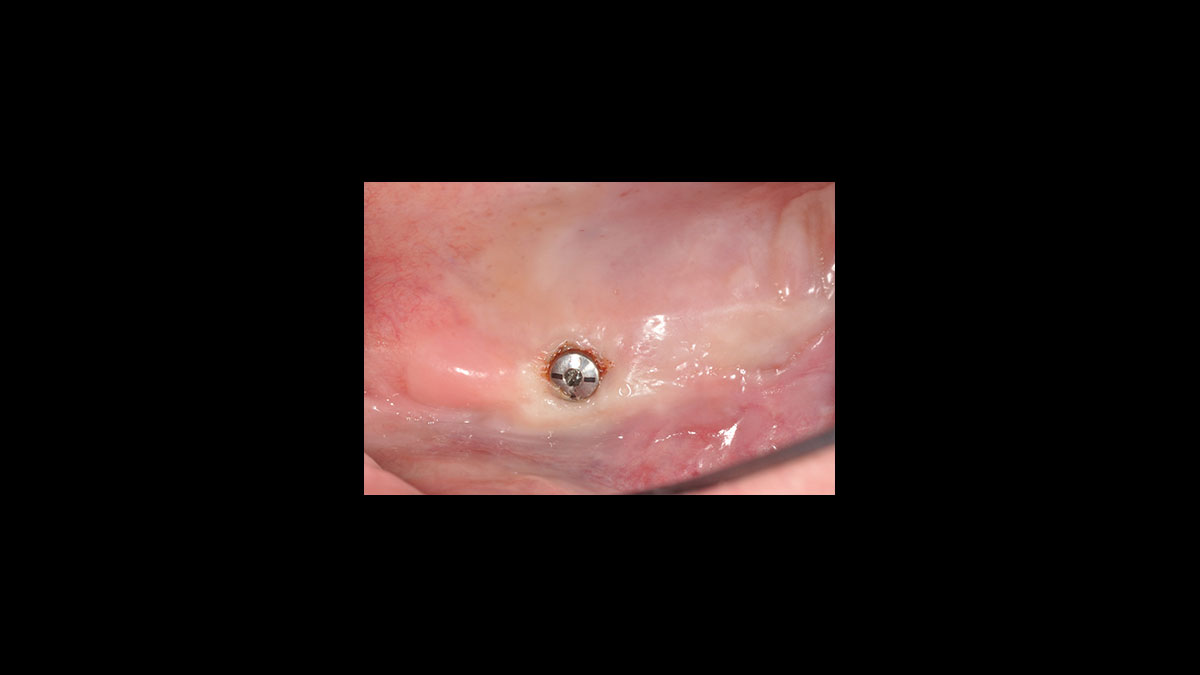

Exposition de l’implant